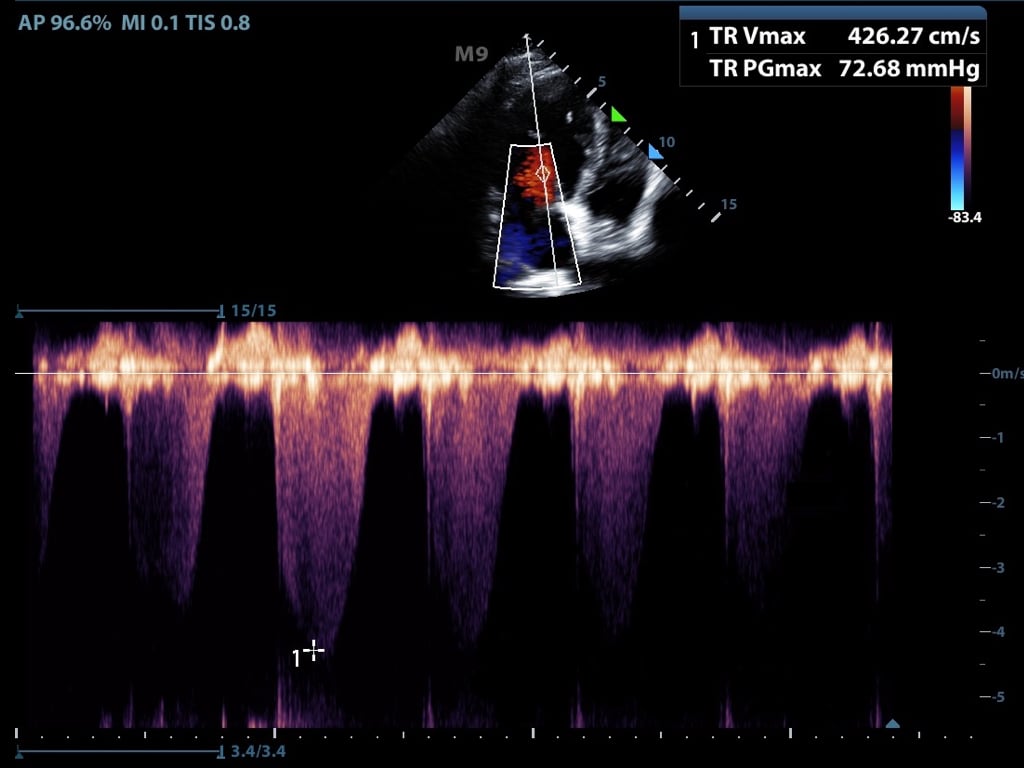

- Continuous wave Doppler

- Transducer continuously sends and receives signals

- This allows for detection of very high frequency signals (Figure 6)

- Velocities along the entire line of interrogation are measured and not localizable

- Figure 6. Continuous flow doppler of tricuspid regurgitation